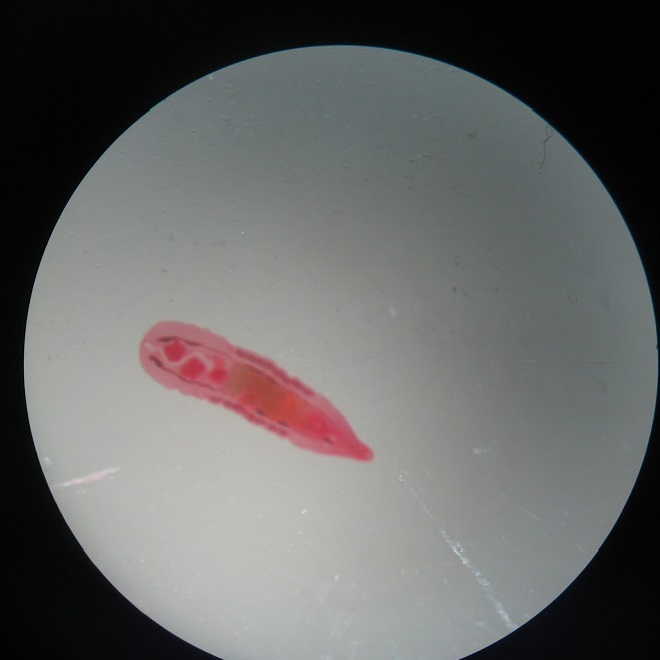

Как выглядит червь описторхоза?

Сам паразит выглядит специфично: внешне это маленький червь длиной до 0,18 см и шириной до 0,02 см. В передней части имеются 2 присоски, которыми паразит крепится к хозяину и передвигается по организму. В задней части гельминта имеются семенники: 2 яруса по 5 и 4 лопастей. В середине тела располагается матка, которая темнее остальной части червя.

Распространение происходит яйцами, которые находятся в матке. Яйца имеют желто серый или желто белый окрас неправильной овальной формы длинной до 30 мк.